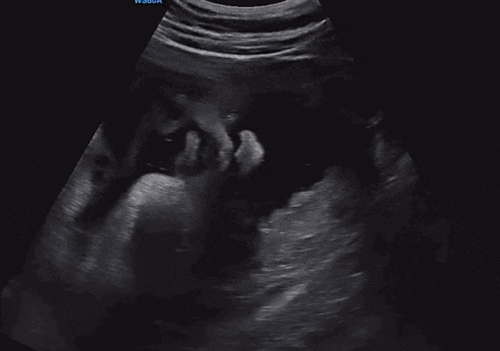

양수 터질때부터 출산까지 타임라인별로 적어본 ✨포도 출산 기록✨ <38주 1일> - 양수 터짐! 갑작스...

마지막 기록이 될 줄 모르고 야금야금 적었던 ✨38주차 기록✨ <38주 0일차> 임신 초기처럼 다시 잠...